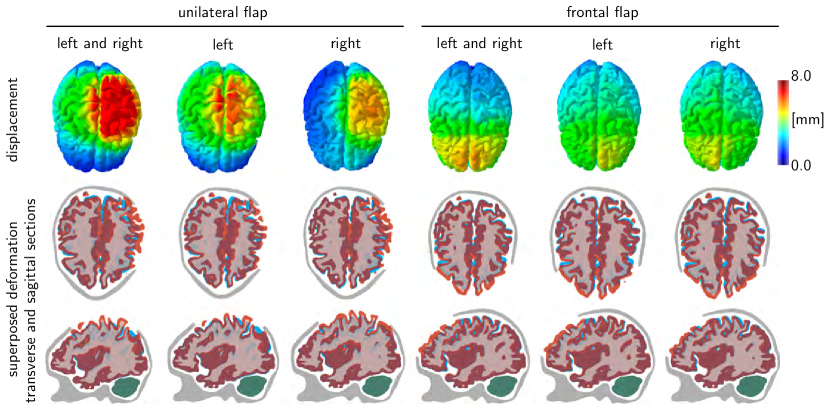

Refer to caption

Figure 7: Decompressive craniectomy. Displacement and superposed deformation in transverse and sagittal sections for unilateral and frontal flaps with left and right, left, and right hemispherical swelling. Swelling causes a shift of intracranial tissues, a key indicator of the trauma’s severity in clinical practice. The midline shift of the cortical and subcortical layers highlights the immediate release of tissue strain upon removal of the unilateral and frontal flaps.

Figure 7 illustrates the displacement and the superposed deformation in transverse and sagittal sections for unilateral and frontal flaps with both left and right, only left, and only right hemispherical swelling. The surgical area available for a frontal flap is about twice as large as the area for a unilateral flap. Consequently, for the same amount of swelling, the displacements of the frontal flap are significantly smaller than for the unilateral flap. This finding is in agreement with our intuition and with our idealized hemidisk simulation in Figure 3, for which larger opening angles generate smaller radial and tangential stretches. The superposed deformation in transverse and sagittal sections in Figure 7 highlights the relative motion of different regions of the brain as the brain bulges outward. Swelling naturally causes a shift of all intracranial tissues. The shift of the midline, which is clearly visible in this sequence of images, is a key clinical indicator for the degree of trauma.